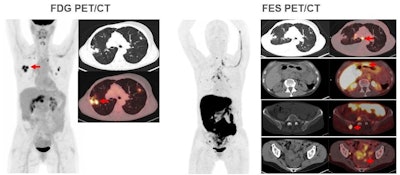

Researchers from California have collected data from 60 patients thus far in an ongoing prospective clinical trial that's comparing PET/CT performed with FES -- an estrogen receptor (ER)-targeting radiotracer -- and current standard-of-care imaging methods for detecting disease in ER-positive breast cancer patients with locally advanced and suspected recurrent disease. So far, they've found FES-PET/CT identifying nodes and metastases that were missed by CT, FDG-PET/CT, ultrasound, and breast MRI.

All patients have undergone either CT bone scans or FDG-PET/CT, followed by FES-PET. Results were evaluated separately to determine the presence of distant metastases in the first group, while the second group's images were used to discover any lesions related to a suspected recurrence. Detected lesions were biopsied, so histology and pathology could serve as the gold standard in head-to-head comparisons of FES-PET, CT bone scans, and FDG-PET/CT.

Among the group of 28 women with suspected cancer recurrence, the site of cancer recurrence was found in eight patients (28%), with the discovery made by FES-PET/CT alone on four women (50%). CT bone scans and FDG-PET/CT only detected distant recurrence in four of the eight patients.